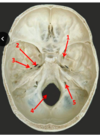

Which arteries do the arrows point to? [1]

A

Lenticulostiate arteries